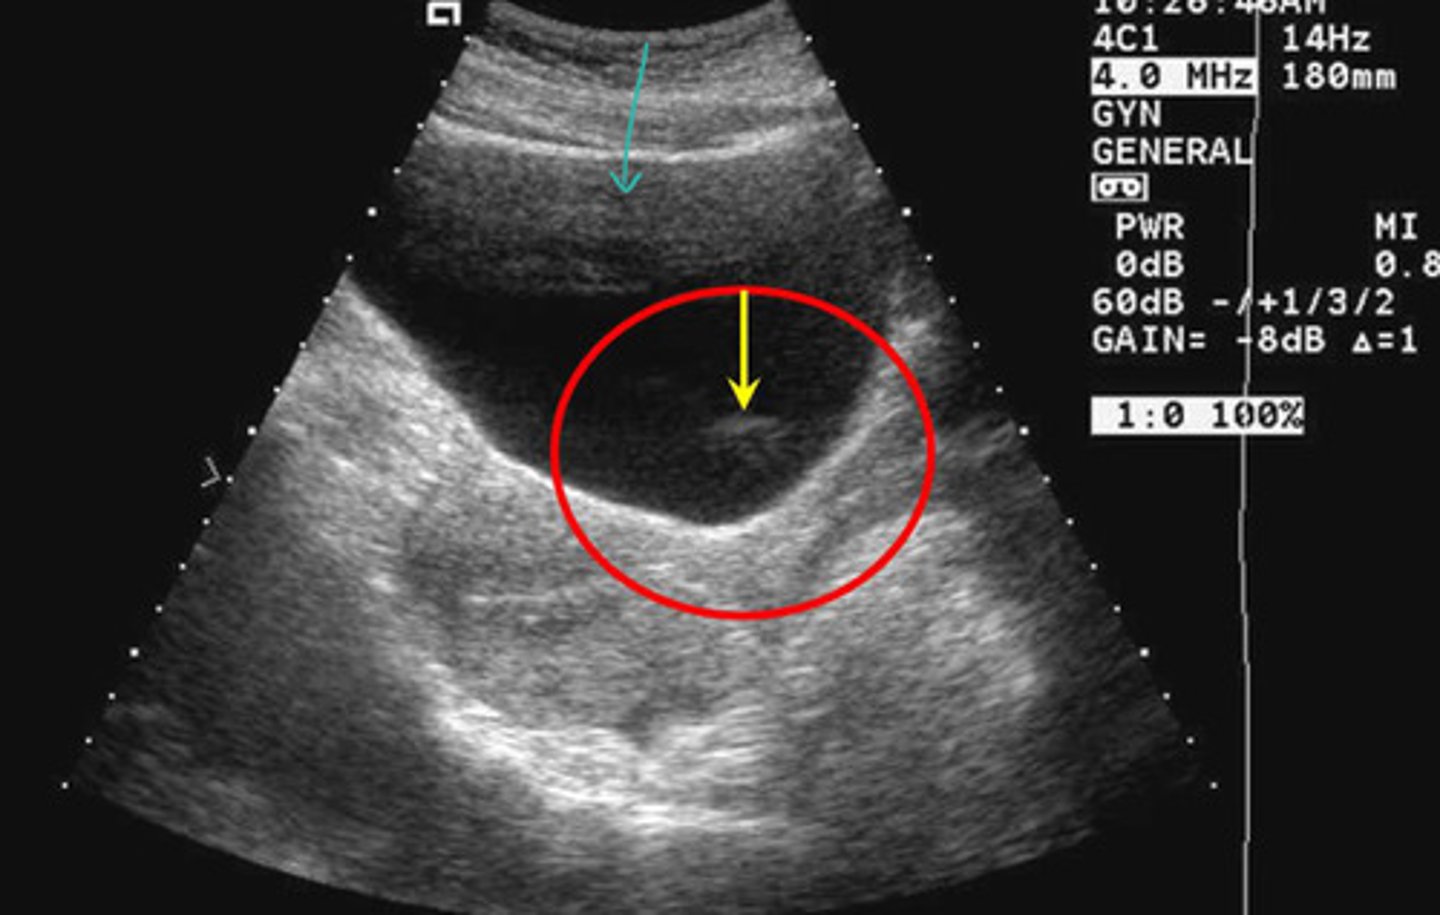

What kind of artifact is the teal arrow pointing to

Side lobes

What kind of artifact is the yellow arrow pointing to